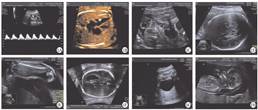

本研究5例胎儿的胎儿超声软指标超声图,见图1。其中,染色体异常组胎儿超声软指标异常为17例(73.9%),染色体正常组为12例(12.0%)。染色体异常组胎儿肠道回声增强和NT增厚发生率,均显著高于染色体正常组,并且差异有统计学意义(P<0.05)。2组胎儿脐静脉导管a波反向、左心室灶状强回声、脉络膜囊肿、肱/股骨偏短发生率分别比较,差异均无统计学意义(P>0.05)。2组胎儿超声软指标比较,见表2。

注:NT为颈项透明层